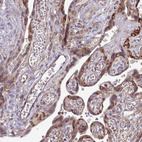

Immunohistochemical staining of human fallopian tube, liver, placenta and testis using Anti-FMR1 antibody HPA050118 (A) shows similar protein distribution across tissues to independent antibody HPA056084 (B).